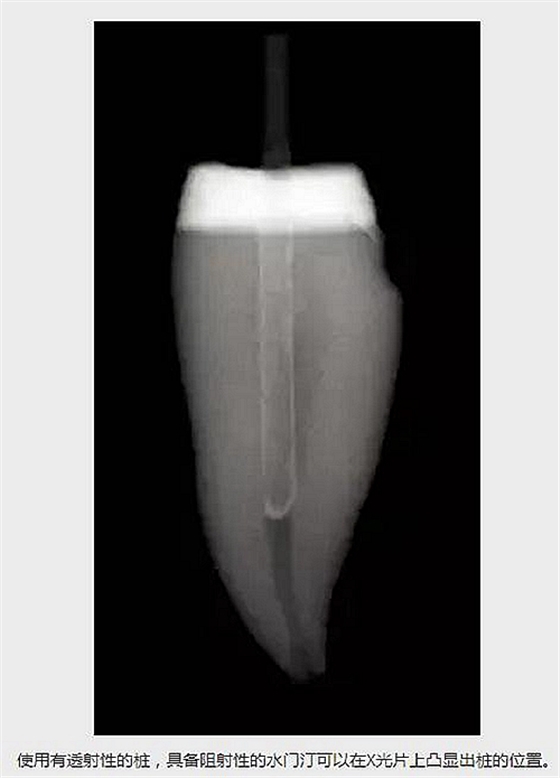

水門汀的阻射性,比如Multilink Automix (Ivoclar /Vivadent)或者使用其他水門汀。如果使用了一個有透射性的樁,有阻射性的水門汀可以在X光片上凸顯出樁的外形。 (見下圖)

使用有透射性的樁,具備阻射性的水門汀可以在X光片上凸顯出樁的位置。